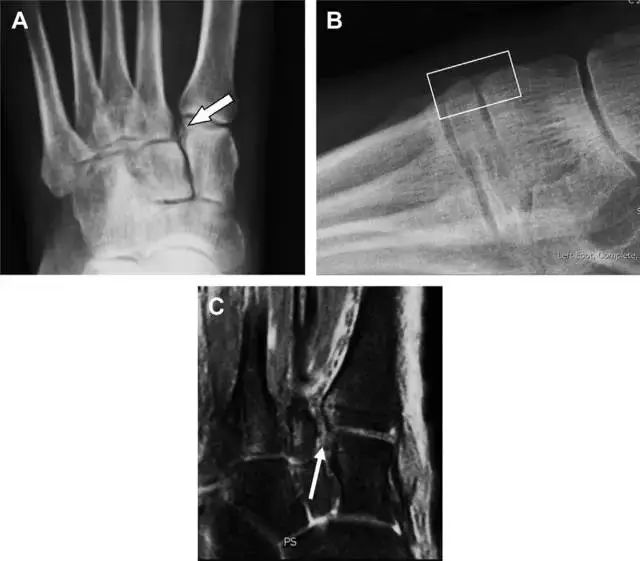

距骨外侧突骨折

距骨外侧突骨折常因踝外翻背屈时,跟骨上外侧面撞击距骨外侧突下缘导致,或偶尔由踝内翻引起,被称为「滑雪板者骨折」。这种骨折只能在踝关节正位片上发现,而且外踝远端表面软组织肿胀往往是一个重要线索(图 4)。

图 4 距骨外侧突骨折。A 正位片示内翻损伤所致的距骨外侧突撕脱性骨折(箭头);B 另一位患者,踝外翻损伤导致典型的「滑雪板者骨折」,X 片上可见一较大的三角形骨折块(方框);C 第二位患者的 MRI 矢状位 T1 加权像示横行骨折(箭头)。

19

距骨后突骨折

距骨后突有内侧结节和外侧结节,距骨后突内侧结节撕脱性骨折常发生在背屈内旋的*力暴**作用下。严重跖屈时,胫骨后缘和跟骨挤压距骨后突外侧结节呈楔形,易发生粉碎性骨折。这些骨折细微且需与三角骨鉴别。侧位片观察距骨后突骨折最佳,常规拍片很难发现,当高度怀疑这种骨折又没法做 CT 时,建议加做多个角度的外旋斜位片(图 5)。

图 5 距骨后突骨折。侧位片(A)和 MRI 矢状位 T1 加权像(B)均示后外侧突的简单骨折(箭头),再次阅片时才发现 X 线片上的骨折;侧位片(C)和 CT 横断面图像示后内侧突的粉碎型骨折(箭头)。

20

跟骨前突骨折

呈 Y 形的分歧韧带附着于跟骨前突上,是维持踝关节跖屈和背屈稳定性的重要结构。跟骨前突骨折常发生于足跖屈内旋、分歧韧带被牵拉时,或者足背屈外旋、骰骨和距骨挤压前突时。而这些骨折在初次 X 线检查时常常被漏诊掉。踝部侧位片诊断这些骨折最佳,准确诊断的关键点在于,必须仔细查看是否存在骨皮质中断(图 6)。如果侧位片可疑,建议加做斜位片协助诊断。

图 6 跟骨前突骨折。A 侧位片示跟骨前突骨折(箭头),与舟骨的重叠使骨折显示模糊;B 另一位患者的侧位片示内翻损伤所致的骨折(箭头),这种损伤机制引起小块的骨折。